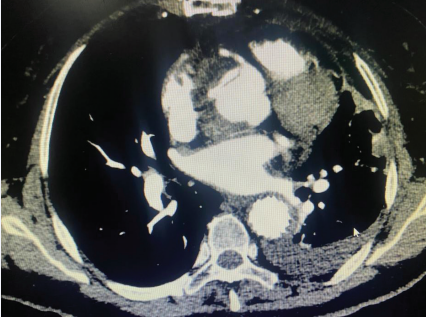

In our cohort, 28 cases of acute type A aortic coarctation underwent intraoperative “modified sandwich” root shaping with artificial vascular slices. Among these cases, 24 patients received total arch replacement with stenting and elephant trunk surgery, 4 patients had ascending aorta replacement with a small curvature of the arch under deep hypothermic shutdown, and 1 patient required coronary bypass grafting due to severe involvement of the right coronary artery opening. All 28 patients successfully completed their surgical treatment. The operative time was 9.5 (8.0 - 12.2) hours, including selective cerebral perfusion time of 23.0 (8.0 - 35.0) minutes, intraoperativeextracorporeal circulation time of 265.0 (210.0 - 322.5) minutes, and aortic occlusion time of 151.0 (112.0 - 209.0) minutes. Postoperative awakening time for 21 patients was 36.0 (33.0 - 81.5) hours, endotracheal intubation time was 88.6 (55.5 - 172.1) hours, and postoperative ICU stay was 124.7 (89.9 - 185.1) hours. There were 2 perioperative deaths (7.1%): one due to renal failure and abdominal ischemia, and the other due to coronary artery causes. At 24 hours postoperatively, serum creatinine (Cr) was 104.19 (81.70 - 149.30) μmol/L, urea was 9.76 (6.44 13.45) mmol/L, total bilirubin was 52.28 ± 24.75 μmol/L, alanine aminotransferase (ALT) was 24.5 (19.0 - 43.0) U/L, and aspartate aminotransferase (AST) was 56.0 (38.0 - 114.0) U/L in 26 patients. Postoperative complications included reopening of the chest for hemostasis in 1 case (3.6%) due to reasons unrelated to the vascular anastomosis, hemodialysis in 3 cases (10.7%), paraplegia in 1 case (3.6%), cerebral infarction with impaired mobility of the left upper extremity in 1 case (3.6%), and tracheotomy in 1 case (3.6%). Of the 26 recovered patients, aortic enhancement CT prior to discharge showed that blood flow through the prosthetic anastomosis was smooth, although 1 case still had residual entrapment in the aortic sinus (Figure 2).

Figure 2 Residual entrapment in the sinus of the aorta.